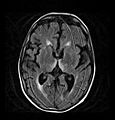

Brain atrophy associated with WKS occurs in the following regions of the brain: the mammillary bodies, the thalamus, the periaqueductal grey, the walls of the 3rd ventricle, the floor of the 4th ventricle, the cerebellum, and the frontal lobe. In addition to the damage seen in these areas there have been reports of damage to cortex, although it was noted that this may be due to the direct toxic effects of alcohol as opposed to thiamine deficiency that has been attributed as the underlying cause of Wernicke-Korsakoff Syndrome.[25]

The amnesia that is associated with this syndrome is a result of the atrophy in the structures of the diencephalon (the thalamus, hypothalamus and mammillary bodies), and is similar to amnesia that is presented as a result of other cases of damage to the medial temporal lobe.[26] It has been argued that the memory impairments can occur as a result of damage along any part of the mammillo-thalamic tract, which explains how WKS can develop in patients with damage exclusively to either the thalamus or the mammillary bodies.[25]

Frequently, secondary to thiamine deficiency and subsequent cytotoxic edema in Wernicke encephalopathy, patients will have marked degeneration of the mammillary bodies. Thiamine (vitamin B1) is an essential coenzyme in carbohydrate metabolism and is also a regulator of osmotic gradient. Its deficiency may cause swelling of the intracellular space and local disruption of the blood-brain barrier. Brain tissue is very sensitive to changes in electrolytes and pressure and edema can be cytotoxic. In Wernicke this occurs specifically in the mammillary bodies, medial thalami, tectal plate, and periaqueductal areas. Sufferers may also exhibit a dislike for sunlight and so may wish to stay indoors with the lights off. The mechanism of this degeneration is unknown, but it supports the current neurological theory that the mammillary bodies play a role in various "memory circuits" within the brain. An example of a memory circuit is the Papez circuit.